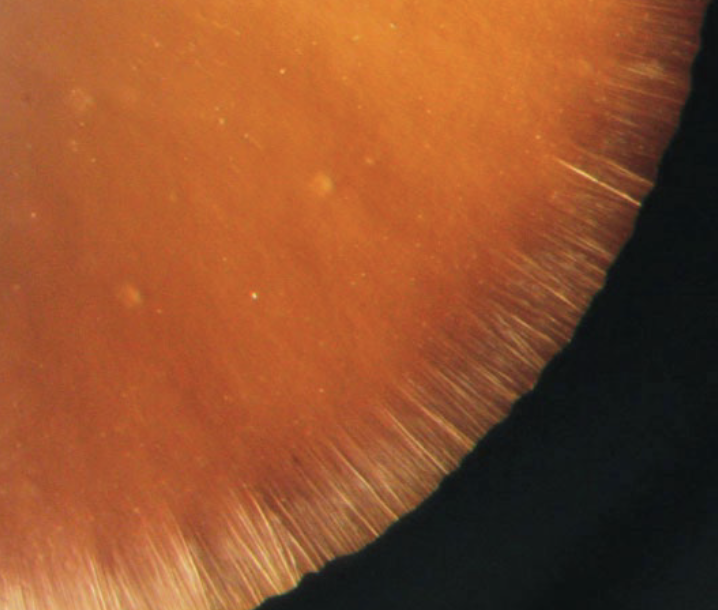

Describe the fibre attachment of the Fetus nucleus.

→ Fibers attach at the anterior & posterior poles

As more fibers form, attachment shifts from a single point to lines → forming Y-shaped sutures

Anterior Y suture: upright (↑)

Posterior Y suture: inverted (↓)

Y-Sutures are created when ends of lens fibers interdigitate (fit together)/interlock from opposite sides of the lens → ensure lens can be continuously reshaped during accommodation

Visibly seen in young adult lenses → become more complex with age as more fibers are added